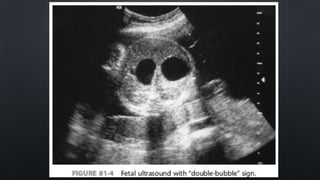

• PRENATAL ULTRASONOGRAPHY DETECT TWO FLUID-FILLED STRUCTURES CONSISTENT

WITH A DOUBLE BUBBLE IN UP TO 44% OF CASES

• MOST CASES OF DUODENAL ATRESIA ARE DETECTED AT BETWEEN 7 AND 8 MONTHS

OF GESTATION

DIAGNOSIS • HISTORY OFPOLYHYDRAMNIOS • PRENATAL ULTRASONOGRAPHY DETECT TWO FLUID-FILLED STRUCTURES CONSISTENT WITH A DOUBLE BUBBLE IN UP TO 44% OF CASES • MOST CASES OF DUODENAL ATRESIA ARE DETECTED AT BETWEEN 7 AND 8 MONTHS OF GESTATION • THE PRESENTATION OF THE NEONATE VARIES DEPENDING ON: • OBSTRUCTION IS COMPLETE OR INCOMPLETE • THE LOCATION OF THE AMPULLA OF VATER IN RELATION TO THE OBSTRUCTION • CLASSIC PRESENTATION  BILIOUS EMESIS WITHIN THE FIRST HOURS OF LIFE IN AN STABLE NEONATE (10% OF CASES THE EMESIS IS NONBILIOUS)